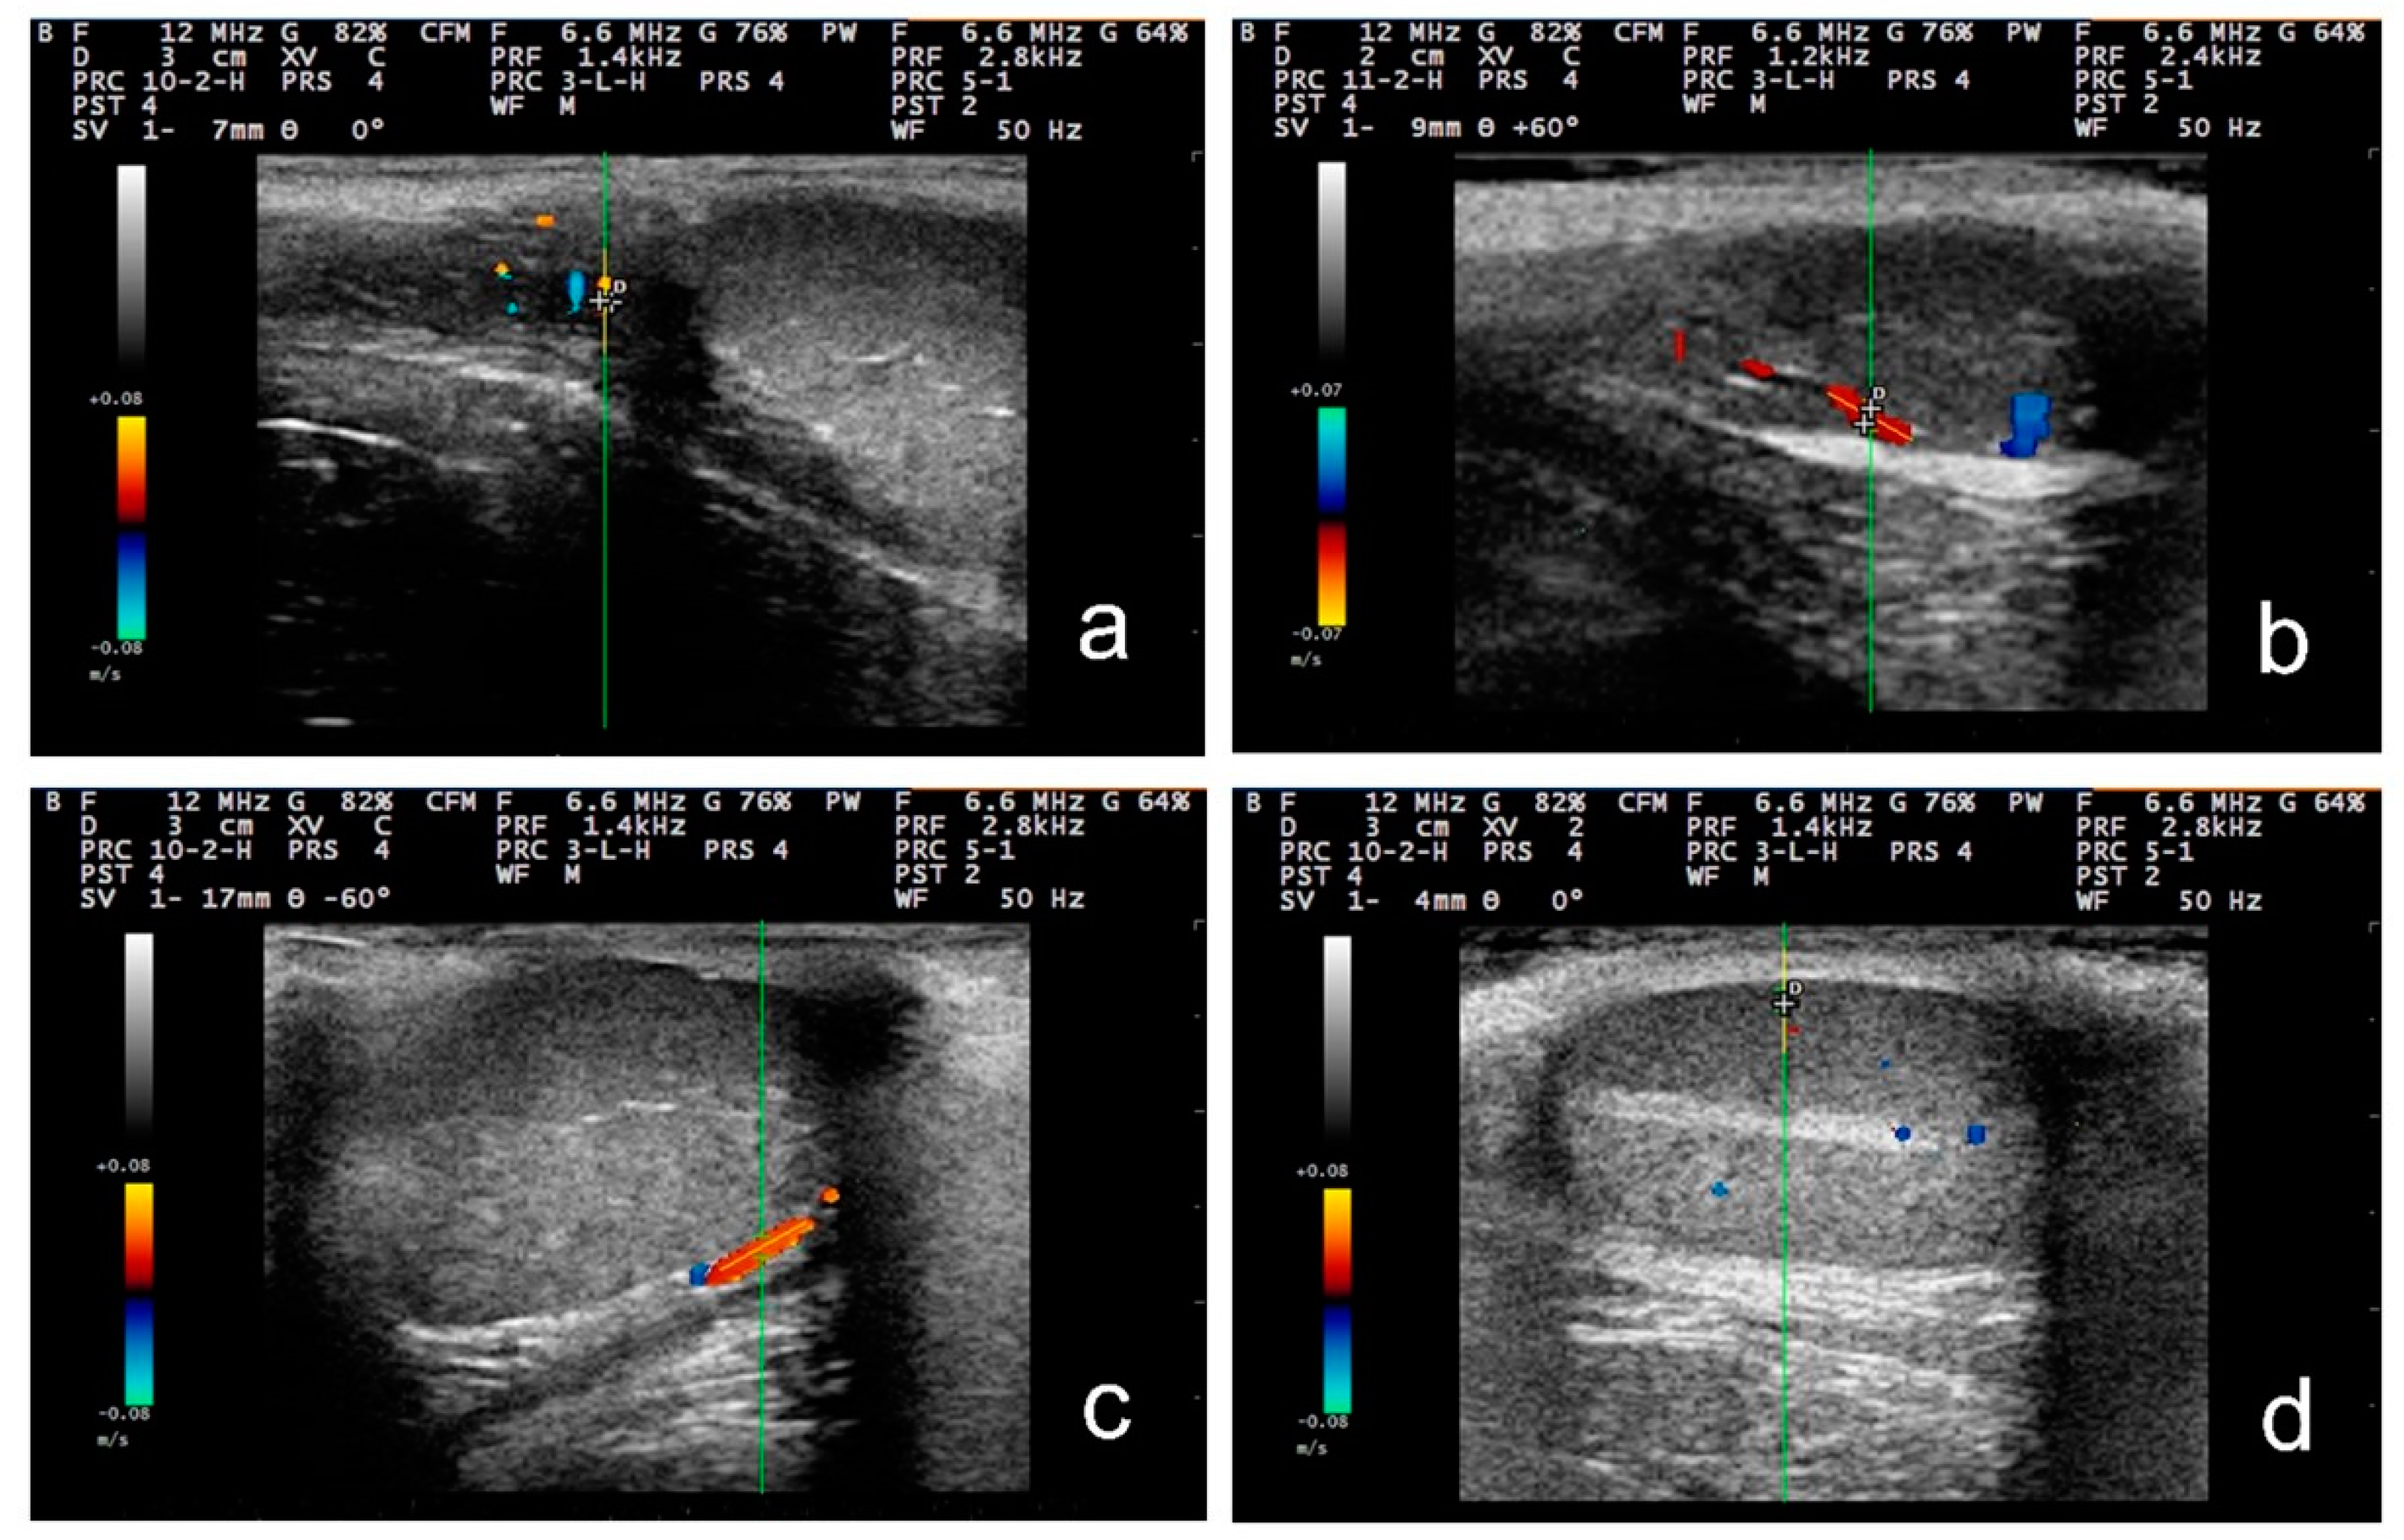

3.3. Pulsed-Wave Doppler

4.2. Differences in the Findings between the Regions of the Testis

4.4. Proposed Segments of the Artery and Haemodynamic Parameters for Doppler Evaluation